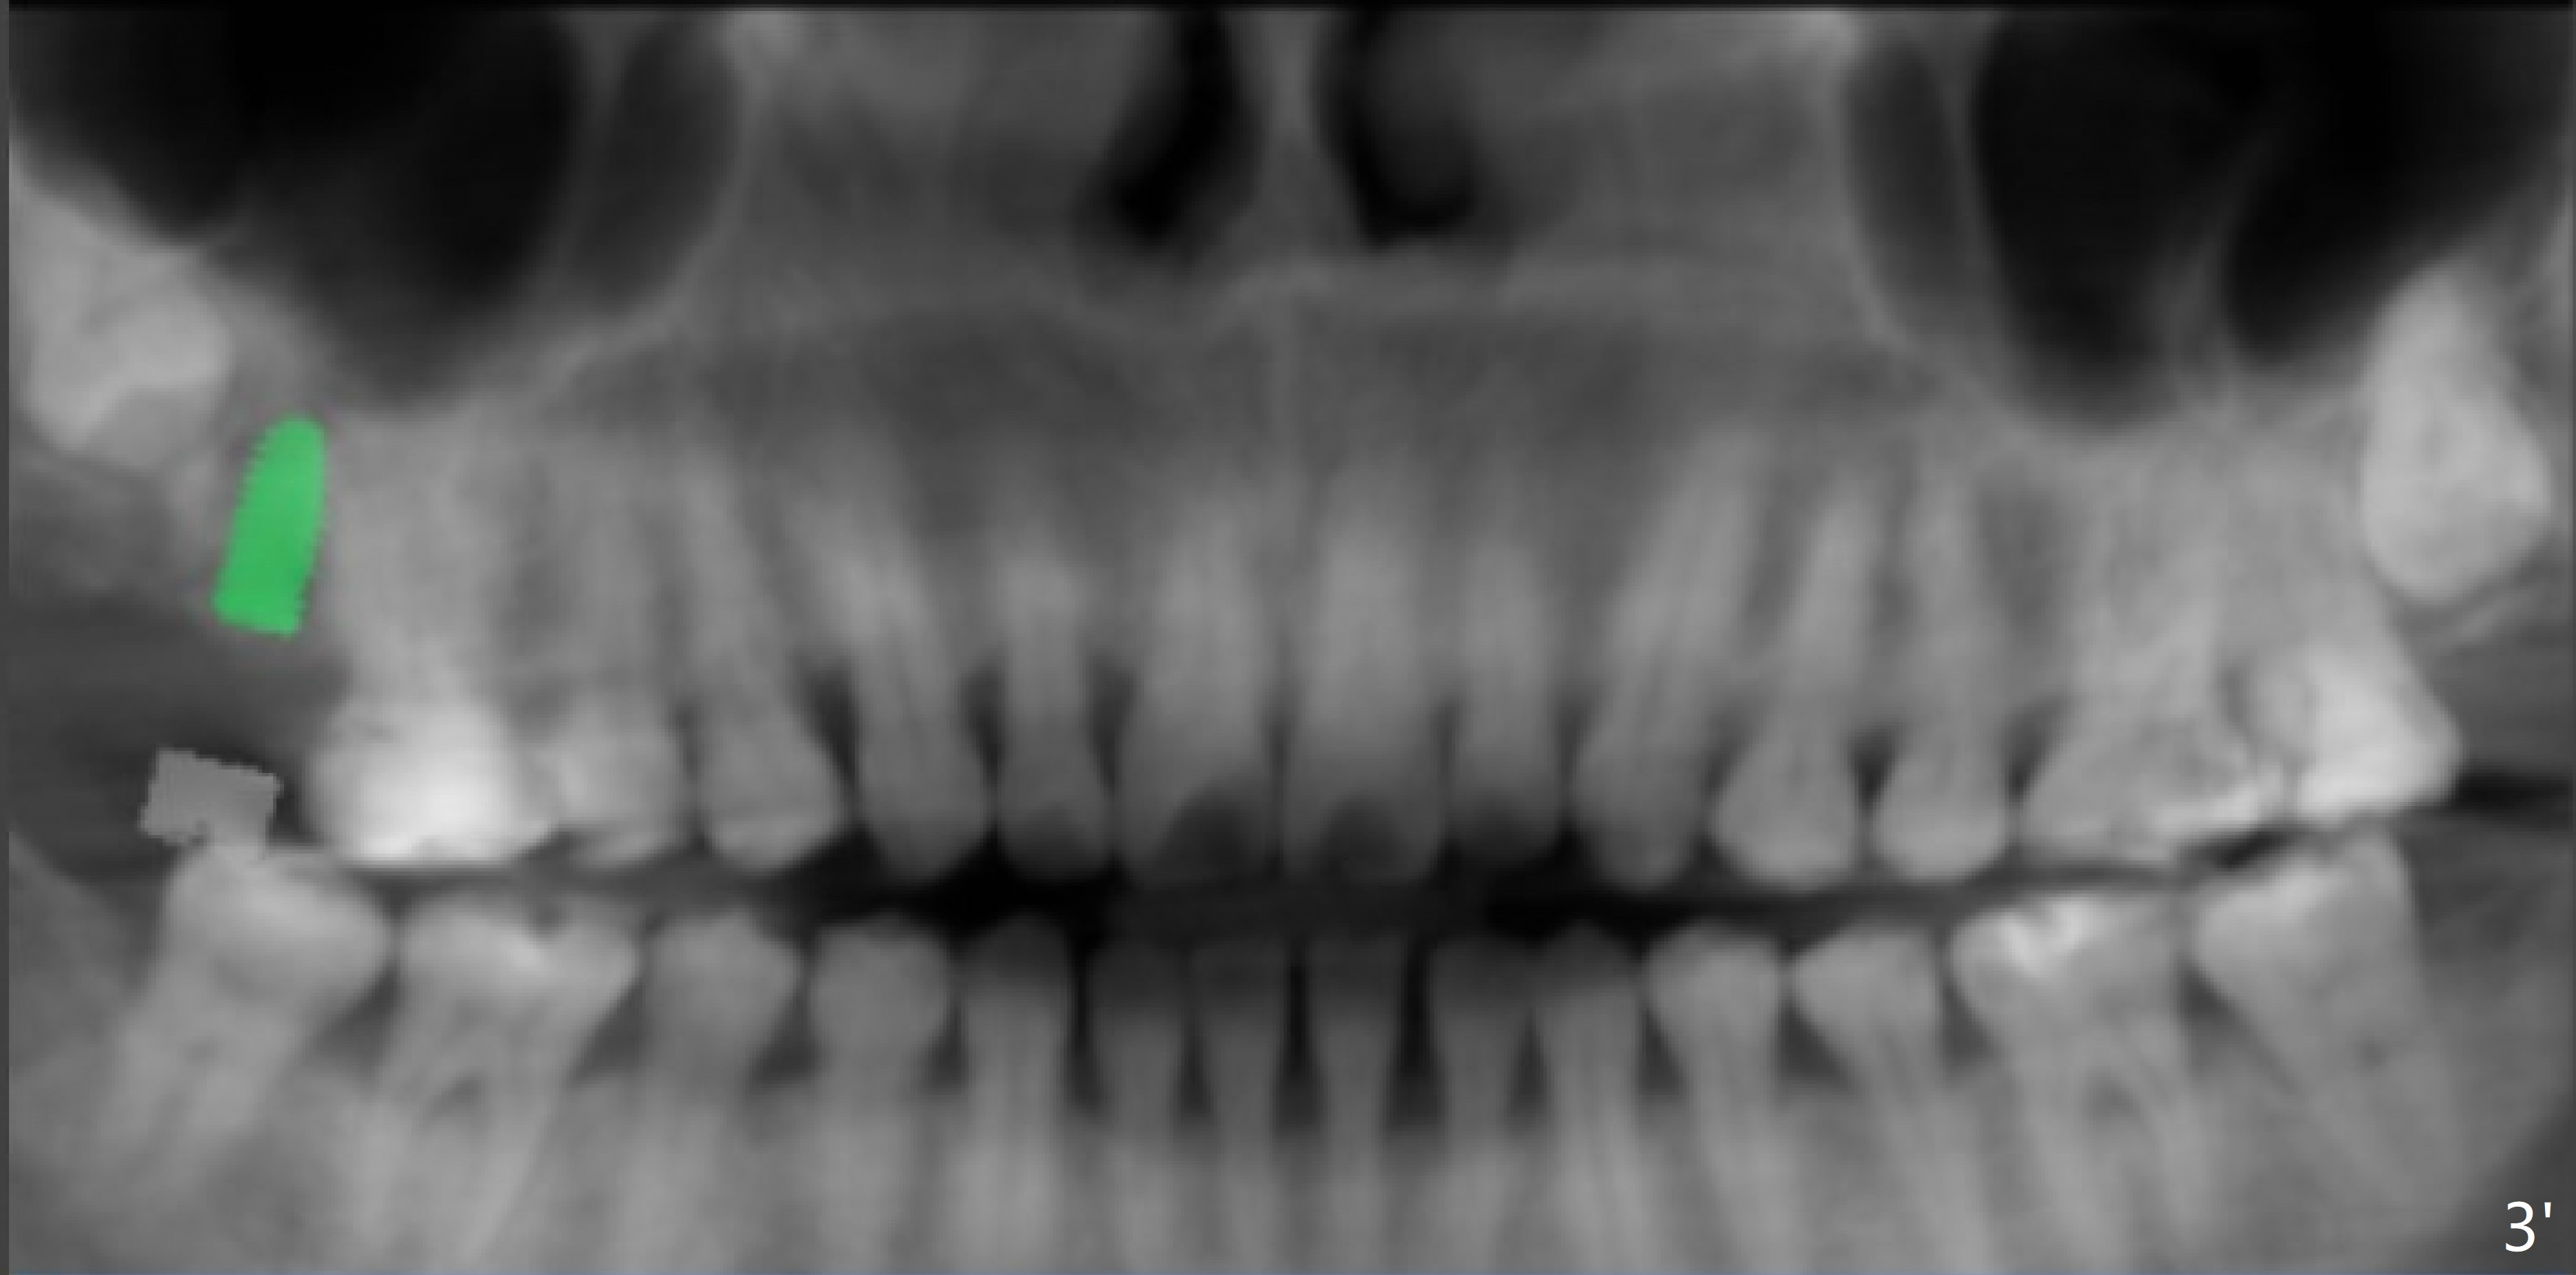

Implant Tilts Distal to Avoid 3rd Molar

A 40-year-old woman requests implant at #2 without removing the impacted 3rd molar (1 year 4 months post socket preservation). In order to do that, the implant should be tilted distal coronally. To reduce screw loosening, use UF implant.